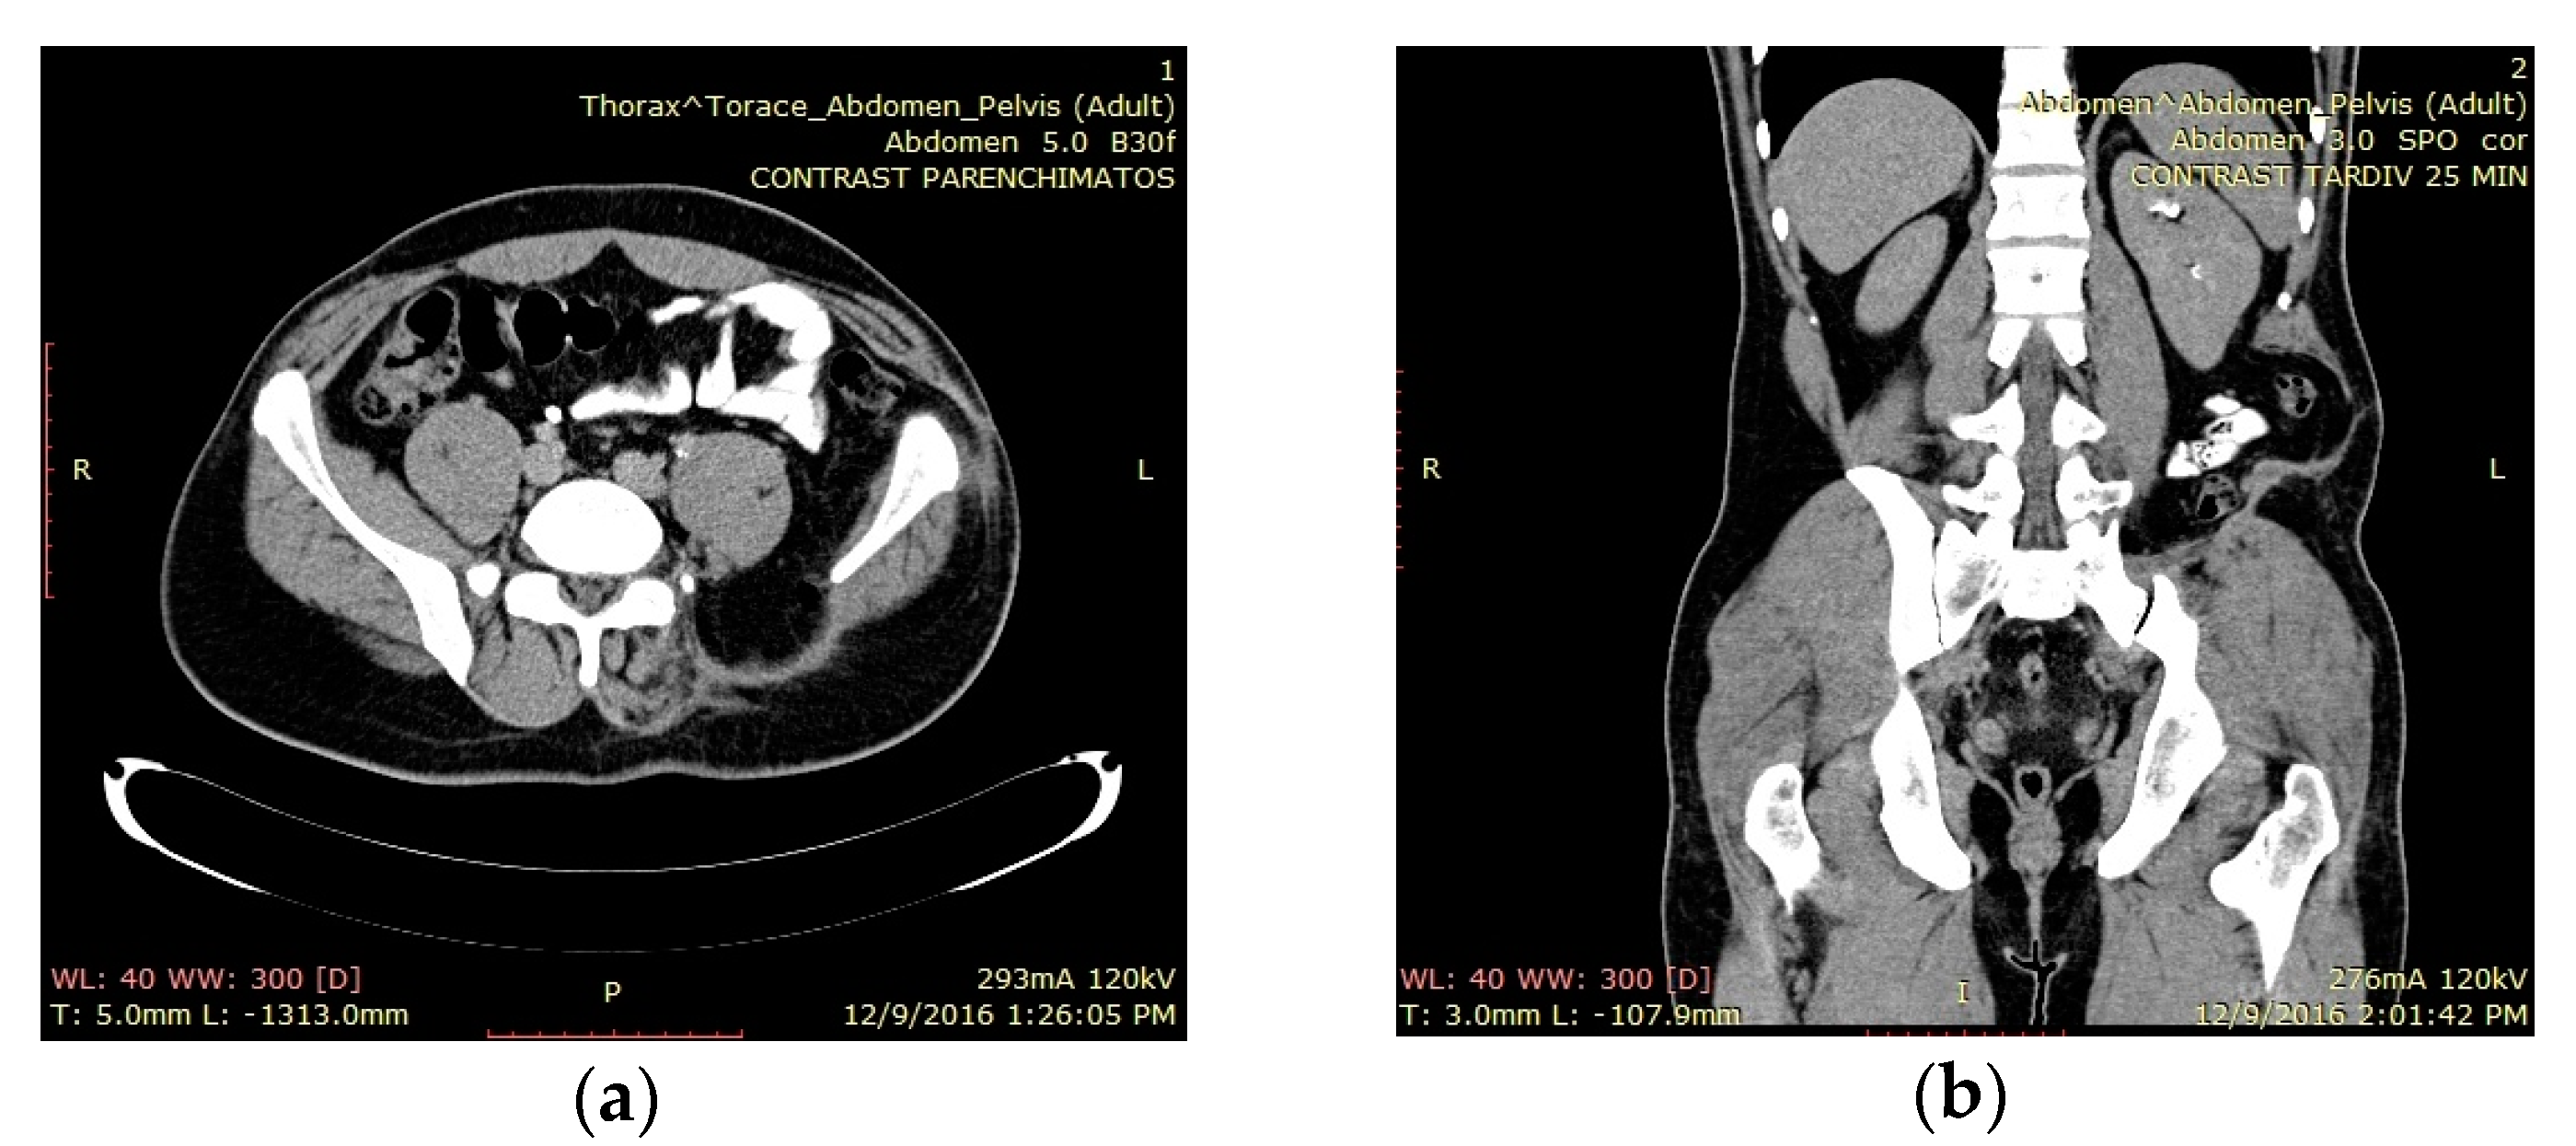

The third case was a 35-year-old male patient with a rare GCT of the posterosuperior iliac bone, including the superior two-thirds of the sacroiliac joint (Figure 3a,b).

Case 3. (a) Preoperative axial T2MRI indicating a left side posterior iliac tumoral mass with no infiltration regarding intrapelvic structures; (b) preoperative sagittal CT scan reveals a posterosuperior osteolytic tumor of the iliac bone involving the sacroiliac joint.

Follow-up was performed at 3, 6 and 12 months and once per year afterwards (36 months maximum). No signs of recurrence were revealed (Figure 5a,b), with a good functional result. The patient returned to work three months following the surgery.

(a,b) Case 3. Axial and coronal pelvic CT scan performed at 18 months postresection, indicating no sign of recurrence.